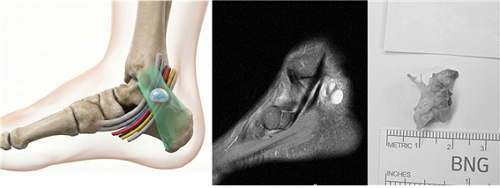

¹ß¸ñÅͳÎÁõÈıº ¸ð½Äµµ(ÁÂ), °áÀýÁ¾À¸·Î ÀÎÇÑ ¹ß¸ñÅͳÎÁõÈıº MRI(Áß°£), Á¦°ÅµÈ °áÀýÁ¾(¿ì)

(ÀÚ·áÁ¦°ø: ÀÇÁ¤ºÎ ¿¬¼¼º£½ºÆ®º´¿ø Àåö¿µ º´¿øÀå)

º¸Á¸Àû Ä¡·á¿¡µµ È£Àü ¾øÀÌ °¨°¢ ÀúÇϰ¡ Áö¼ÓµÇ°í, MRI ¹× ÃÊÀ½ÆÄ µî ¿µ»óÀÇÇÐ °Ë»ç¿¡¼­ °áÀýÁ¾°ú °°Àº ¸íÈ®ÇÑ ¾Ð¹Ú ¿øÀÎÀÌ È®ÀÎµÈ °æ¿ì¿¡´Â ¼ö¼úÀû Ä¡·á¸¦ °í·ÁÇÒ ¼ö ÀÖ´Ù. ¼ö¼úÀº ¹ß¸ñÅͳÎÀ» µ¤°í ÀÖ´Â ±¸Á¶¹°À» À¯¸®¡¤°¨¾ÐÇÏ¿© ½Å°æÀÌ Áö³ª°¡´Â °ø°£À» ³ÐÇôÁÖ´Â ¡®¹ß¸ñ ÅͳΠÀ¯¸®¼ú¡¯ÀÌ Áß½ÉÀÌ´Ù. ¾Ð¹ÚÀÇ ¿øÀÎÀÌ µÇ´Â °áÀýÁ¾À̳ª Á¾±«°¡ ÀÖ´Ù¸é µ¿½Ã¿¡ Á¦°ÅÇÏ´Â ¡®Á¦°Å¼ú¡¯À» ÇÔ²² ÁøÇàÇÑ´Ù. ¼ö¼úÀÇ ÇÙ½ÉÀº ½Å°æÀÌ Áö³ª°¡´Â °ø°£À» ÃæºÐÈ÷ È®º¸Çϰí, ¾Ð¹Ú ¿øÀÎÀ» Á¦°ÅÇÏ´Â °ÍÀÌ´Ù.